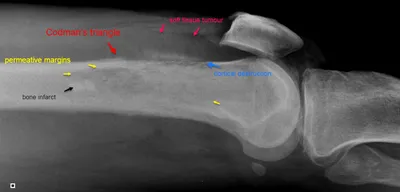

Osteosarcoma Radiology Images

This collection contains 1 radiology images related to osteosarcoma, including various imaging modalities such as X-rays, MRIs, CT scans, and ultrasound images commonly used in medical diagnosis and education.